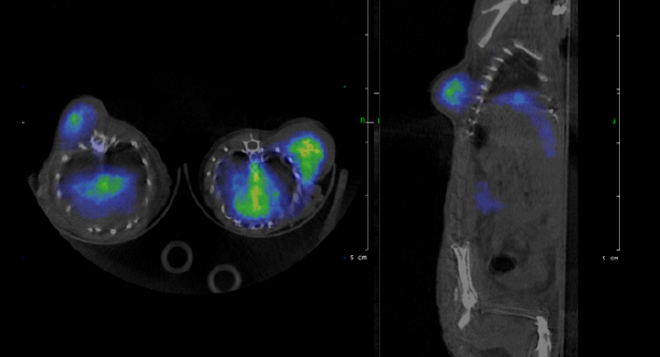

Formation : imagerie isotopique préclinique µSPECT et µTEP

Jusqu'au 17 mars 2017

La Faculté de Pharmacie (Aix-Marseille Université) organise en collaboration avec le Centre Européen de Recherche en Imagerie Médicale (CERIMED) une formation certifiante d’excellence en imagerie isotopique préclinique µSPECT et µTEP (CESU, 63h sur 10 jours).